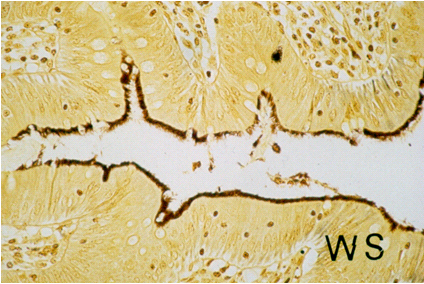

In 1967, Harland and Lee coined the term intestinal spirochetosis (IS), recognizing the adherence of spirochetes to colorectal epithelium in histology and electron microscopy, the characteristic appearance that is still considered pathognomonic for a possible capacity to cause human disease [2] (Figure 1 [Fig. 1], Figure 2 [Fig. 2], Figure 3 [Fig. 3], Figure 4 [Fig. 4], Figure 5 [Fig. 5]). Despite improvements in the detection and identification of IS, it is still unclear whether this condition represents an actual disease process, or rather, the organisms represent interesting intestinal colonizers in men that does exclusively manifest in the large bowel.

Figure 4: Immunohistochemical detection of human intestinal spirochetosis with signs of invasion. Strept-Avidin technique. x680.

The diagnosis of IS is traditionally based on the histological appearance of a diffuse blue fringe (seen in hematoxylin-eosin stain), which is approximately 3 to 6 μm thick, along the border of the intercryptal epithelial layer. This finding is referred to as the “false brush border” [2], [4] (Figure 2 [Fig. 2]). When IS is suspected on the basis of finding a blue fringe, Warthin-Starry or Dieterle silver impregnation stains can be used to highlight the spirochetes in fixed tissue samples (Figure 3 [Fig. 3]) [4], [36], [43], [44], [45], [46], [47], [48], [49], [50], [51], [52]. Recently, an antibody against Borrelia burgdorferi has been applied in the immunohistochemical detection of IS [53] (Figure 4 [Fig. 4]). This is a great diagnostic advantage.